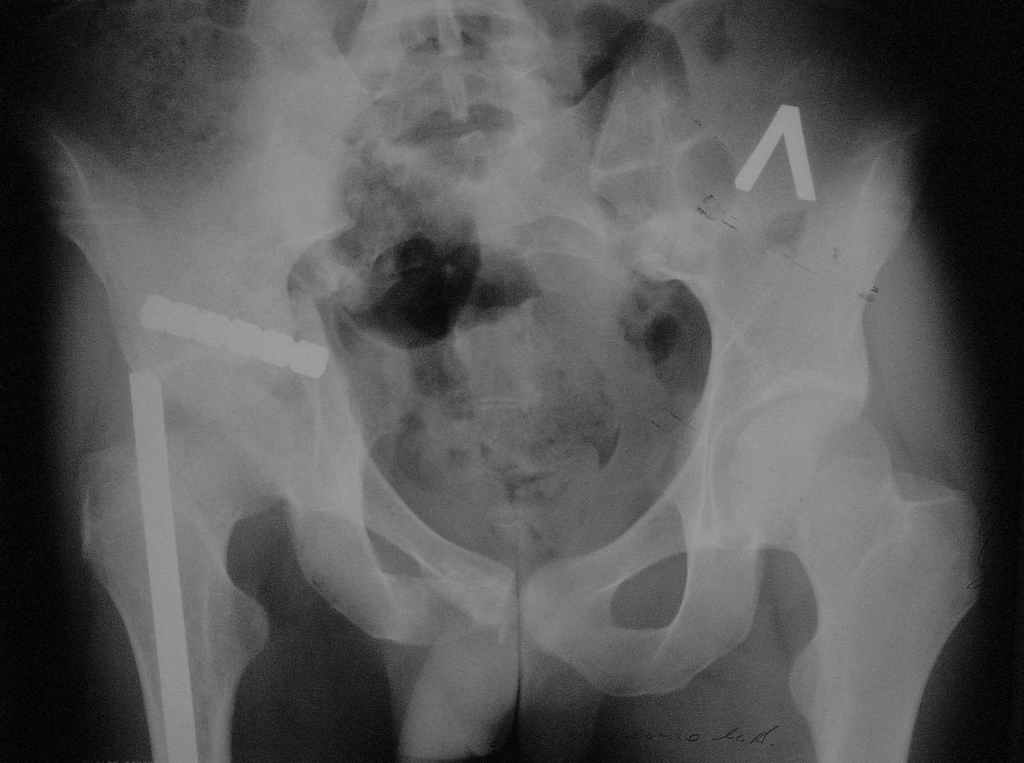

По прямой проекции - Вертикальная стабильная (?) деформация таза IIIст., неправильно сросшийся (?) перелом боковой массы крестца справа, неправильно сросшийся поперечный (?) перелом првавой вертлужной впадины.

В любом случае смещение задних отделов более 2-3 см у молодого человека является показанием к его устранениию. План лечения требует данных полипроекционной рентгенографии и кт задних отделов и вертлужной впадины.

Вероятный план: остеотомия лонной и седалищной костей справа, остетомия или закрытый разрыв крестца в кольцевом аппарате, низведение и компрессия половины таза, илиосакральное блокирование справа.

Пример лечения стабильной деформации с вертикальным смещением половины таза.

отеотомия передних и задних отделов, дистракция аппаратом

окончательная фиксация